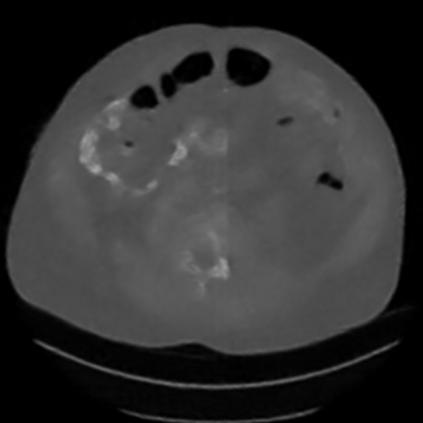

Sparse-view computed tomography (CT) -- using a small number of projections for tomographic reconstruction -- enables much lower radiation dose to patients and accelerated data acquisition. The reconstructed images, however, suffer from strong artifacts, greatly limiting their diagnostic value. Current trends for sparse-view CT turn to the raw data for better information recovery. The resultant dual-domain methods, nonetheless, suffer from secondary artifacts, especially in ultra-sparse view scenarios, and their generalization to other scanners/protocols is greatly limited. A crucial question arises: have the image post-processing methods reached the limit? Our answer is not yet. In this paper, we stick to image post-processing methods due to great flexibility and propose global representation (GloRe) distillation framework for sparse-view CT, termed GloReDi. First, we propose to learn GloRe with Fourier convolution, so each element in GloRe has an image-wide receptive field. Second, unlike methods that only use the full-view images for supervision, we propose to distill GloRe from intermediate-view reconstructed images that are readily available but not explored in previous literature. The success of GloRe distillation is attributed to two key components: representation directional distillation to align the GloRe directions, and band-pass-specific contrastive distillation to gain clinically important details. Extensive experiments demonstrate the superiority of the proposed GloReDi over the state-of-the-art methods, including dual-domain ones. The source code is available at https://github.com/longzilicart/GloReDi.